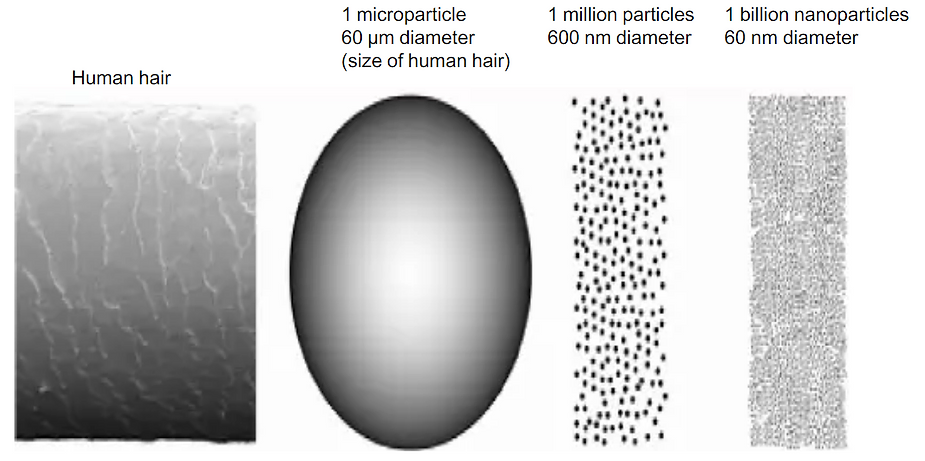

Toxicity of Graphene Family Nanomaterials

Toxicity of Graphene Family of Nanomaterials

Toxicity of Graphene Family of Nanomaterials in Cell Models

Toxicity of Graphene of Family of Nanomaterials in Cell Models

Graphene Family Nano-materials trigger local and systemic toxic effects, induce genotoxicity in vitro and in vivo, alter the gut microbiome, cause genetic mutations, and are inedible. Further toxicological and risk assessment studies are needed especially when used in food or injections of any type.

Graphene, Graphene Oxide (GO), carbon nano-tubes, and the entire graphene-family nano-materials (GFN) are toxic in almost all their forms, causing mutagenesis (cancer, chromosomal alteration), cell death, apoptosis, necrosis, and the release of free radicals.

Several typical mechanisms underlying Graphene Oxide nano-material’s toxicity have been revealed in numerous studies including my own, for instance, physical destruction, oxidative stress, DNA damage, inflammatory response, apoptosis, autophagy, and necrosis. In these mechanisms, toll-like receptors, transforming growth factor-beta (TGF-β) and tumor necrosis factor-alpha (TNF-α) dependent-pathways are involved in the signaling pathway network, and oxidative stress plays a crucial role in these pathways.

Many experiments have shown that Graphene Oxide nano-materials have toxic side effects in many biological applications.

According to the USA FDA, graphene, Graphene Oxide, and reduced graphene oxide elicit toxic effects both in vitro and in vivo.

Graphene-family nano-materials (GFN) are not approved by the USA FDA for human consumption.